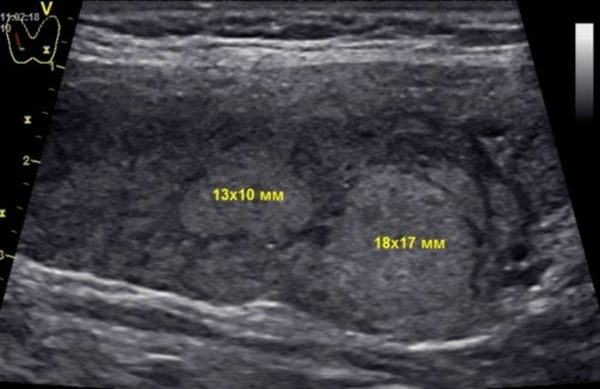

Киста

В ультразвуковой диагностике киста щитовидной железы выглядит как округлое анэхогенное или гипоэхогенное образование с однородной или неоднородной структурой (включает более плотные элементы). Очаг четко отделен от окружающих тканей и имеет капсулу, окрашиваясь в темно-серый или черный цвет. Кисты могут быть как одиночными, так и множественными, образуя скопления. Их размер варьируется от нескольких миллиметров до нескольких сантиметров. Крупные кисты могут вызывать синдром зоба различной степени выраженности и требуют дополнительной диагностики, включая биопсию для определения морфологических характеристик.